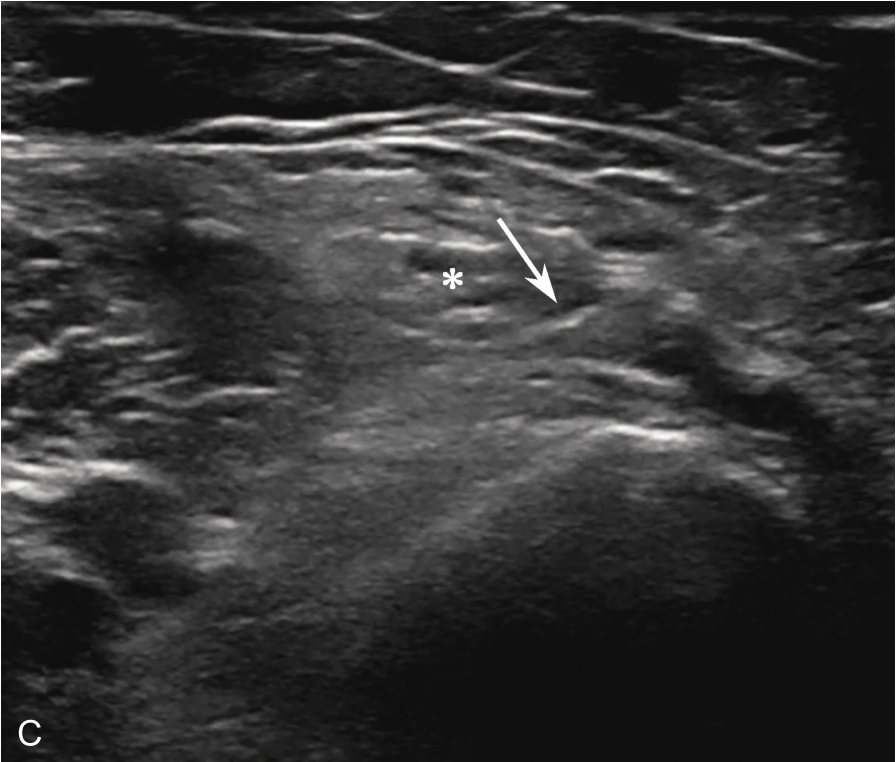

▲ 图2-1-5 超声引导下肩峰下-三角肌下滑囊穿刺治疗超声图

箭头:显示穿刺针尖进入滑囊;星号:冈上肌腱;H:肱骨头